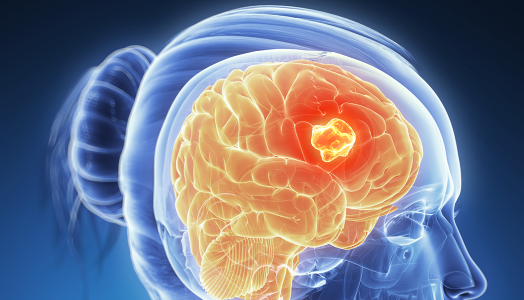

featured Malignant brain tumour (brain cancer)